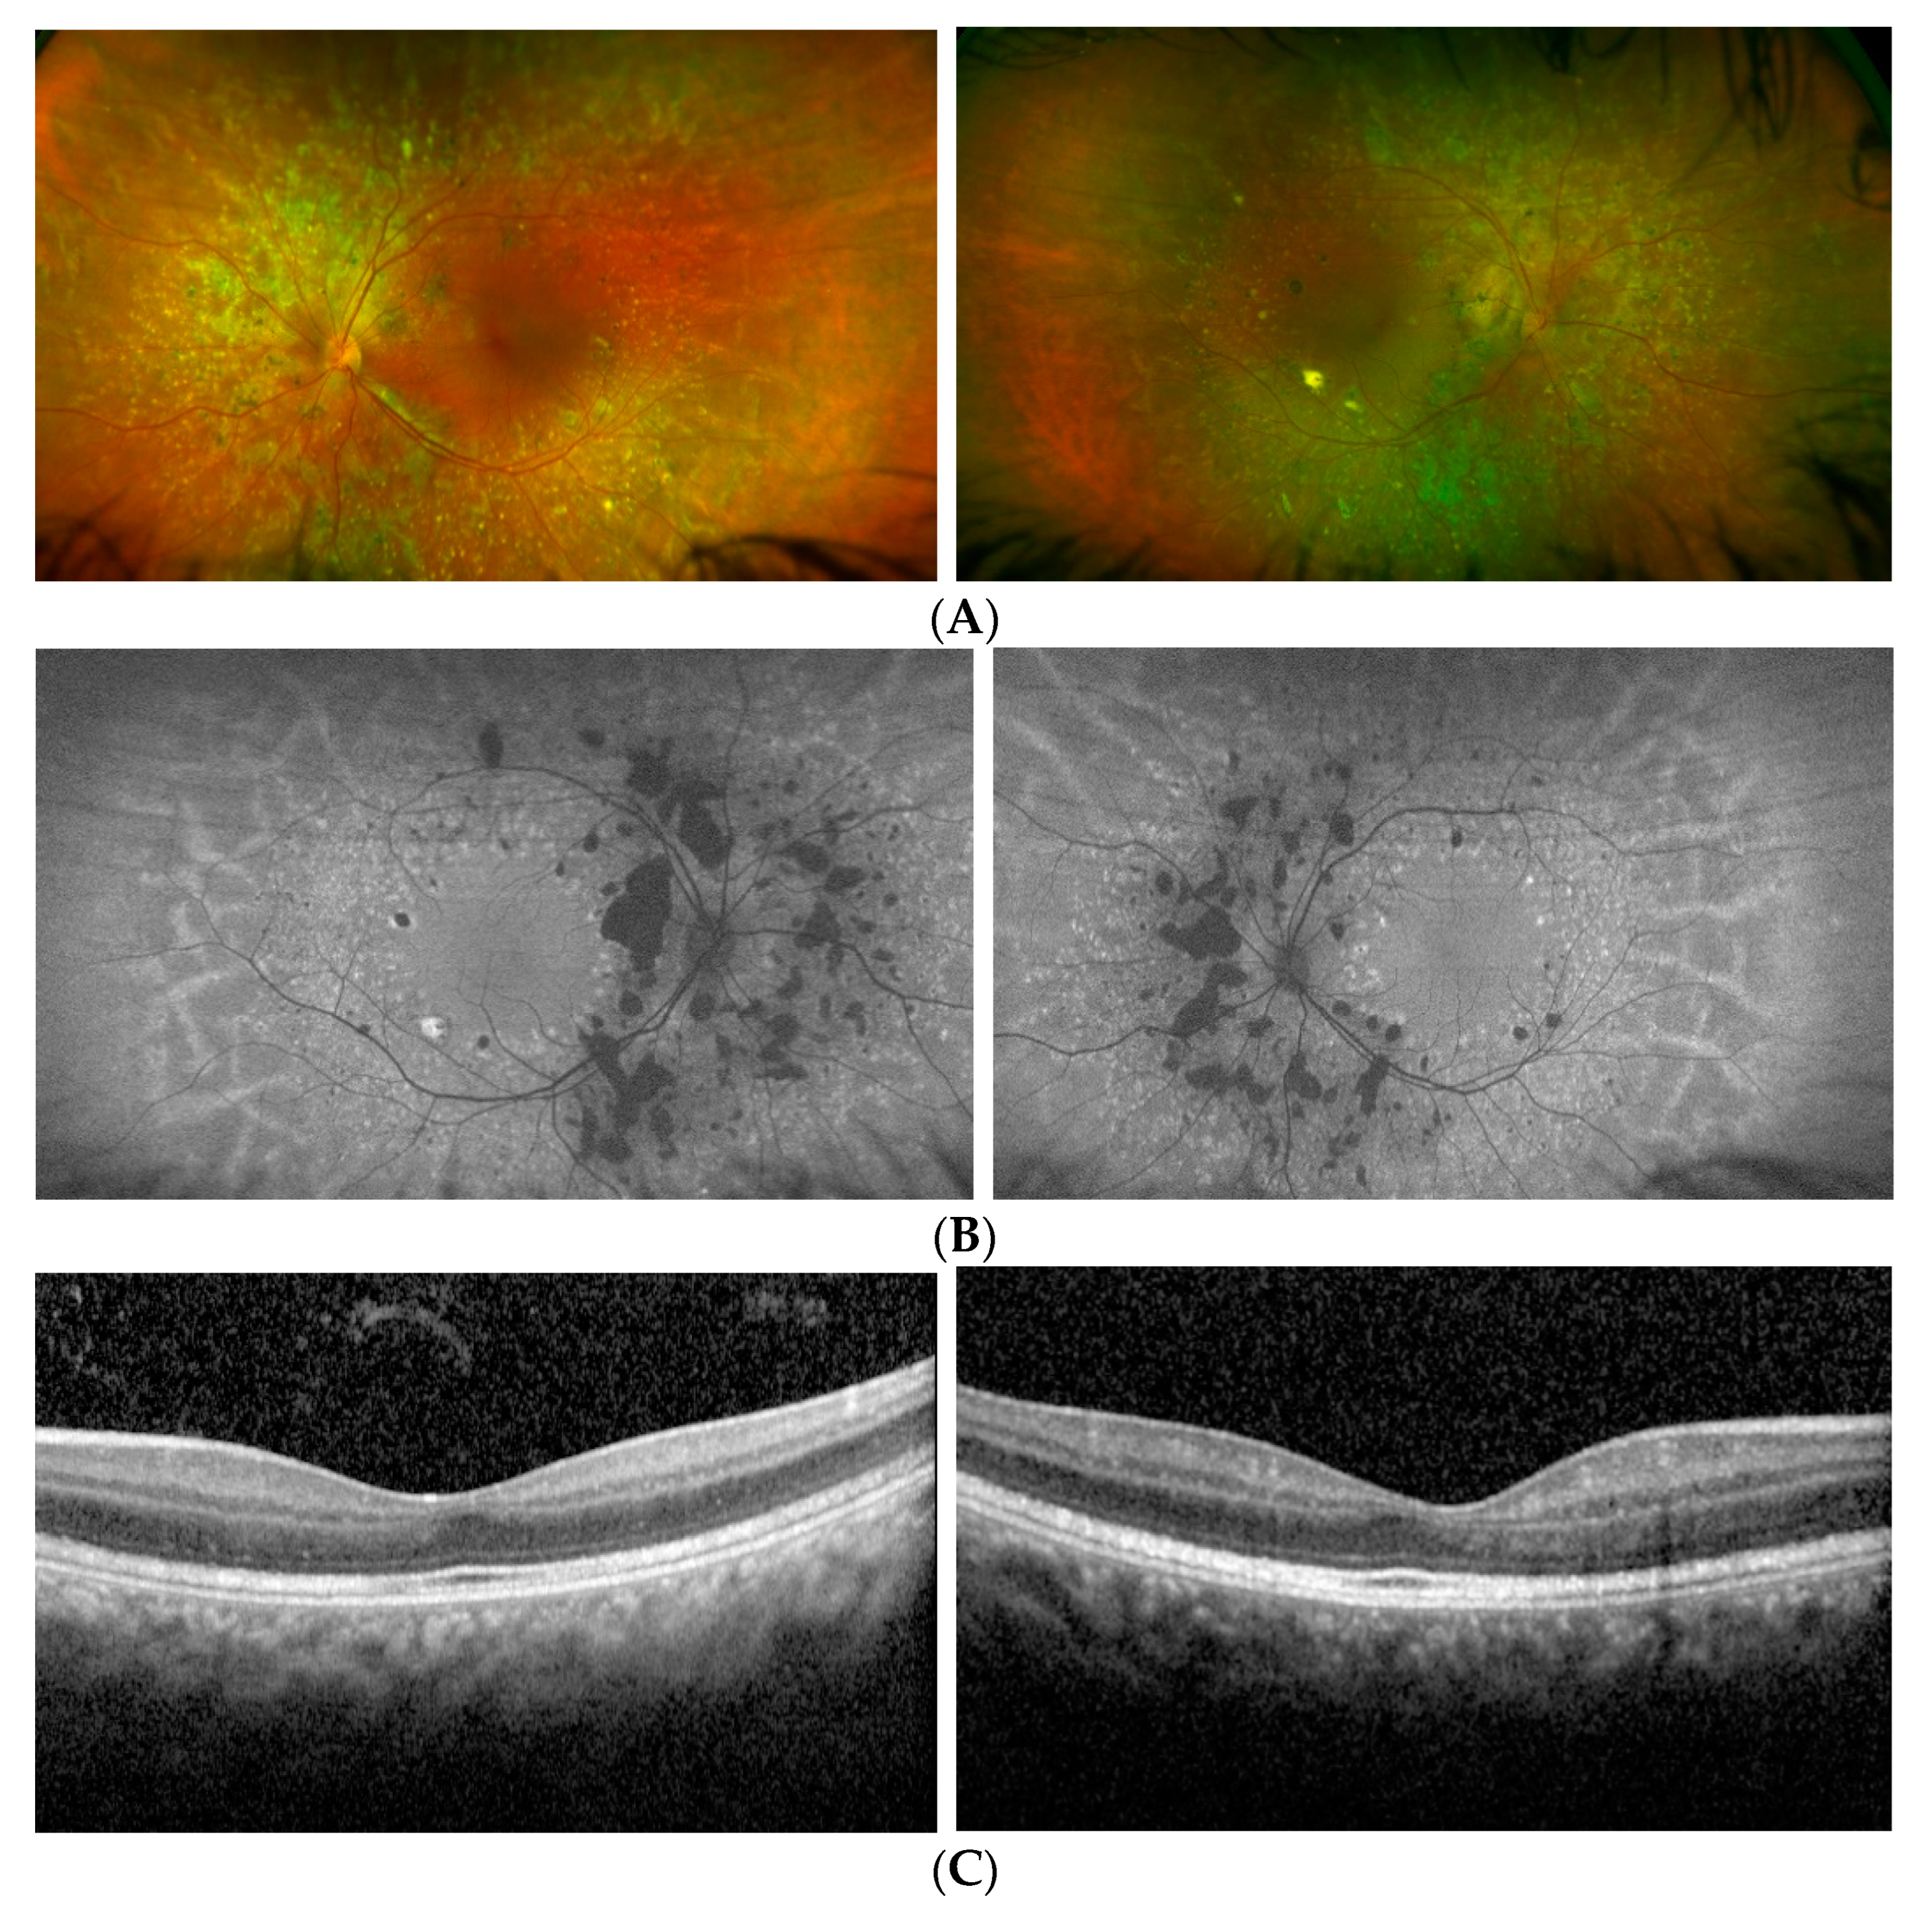

3.1. Patients’ Clinical Reports